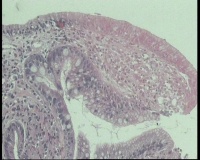

请老师看看胃角溃疡,上皮有轻度非典型增生吗?

性别年龄58岁临床诊断胃角溃疡

一般病史胃角:近后壁见一处圆形溃疡,大小0.6x0.6厘米,底附黄白苔,周围粘膜充血水肿

标本名称胃镜活检

大体所见胃镜活检组织

镜下胃粘膜腺体肠化,局灶腺上皮细胞核大

有坏组织,符合溃疡,腺体肠化,轻度不典型增生。

溃疡+萎缩+肠化+修复。

有肠化和修复性增生。